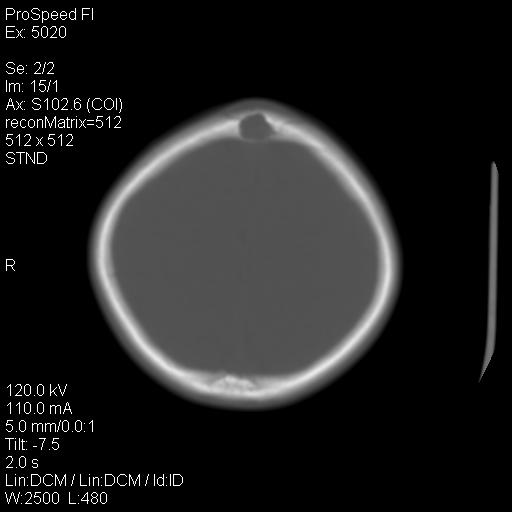

标题: PED1637:M 6Y 顶部无痛性包块两月。 [打印本页]

标题: PED1637:M 6Y 顶部无痛性包块两月。

2、颅骨局部缺失,边缘光滑、整齐

颅骨的病损表现为内外颅骨板层不规则的锋利的破坏,形成“斜边缘”,有一定的特点

颅骨为好发部位,生长缓慢,常位于顶骨、枕骨及颞骨,表现为颅骨缺损,呈圆形或椭圆形,边界清,无硬化